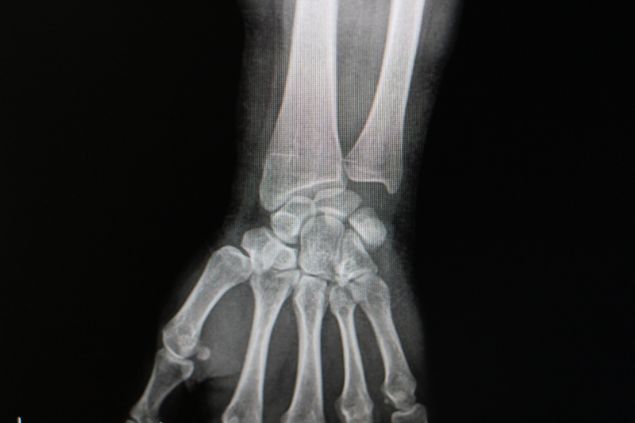

AMASYA’nın Merzifon ilçesinde vücudunda iğne şeklinde metal cisimler çıkan genç kız, aynı şoku 8 yıl sonra yeniden yaşadı.

Genç kızı hastaneye götürdüklerinde kolunda metal cisimler olduğunu öğrenmeleri üzerine şaşıran komşuları Arslan Kurkmazlı da, “Duyan herkes hayret ediyor. ‘Öyle bir şey olur mu?’ diyorlar. Normal iğne ama ucu, dibi yok” diye konuştu.

Doktorlar ameliyatla iğneleri almıştı. Aradan 8 yıl geçtikten sonra kolumda morluklar oldu. Doktora gittik. ‘Ezilme var’ dedi. Bir ay sargıda kaldı. Ağrılar sürünce iğne olduğu anlaşıldı” dedi.

MUHTEMELEN METABOLİK BİR HASTALIK: Ortopedi servisine başvuran Sevda Topkök’ün çekilen röntgen görüntülerinde kolunda cisimlere rastlandığını doğrulayıp hastalarını üniversite hastanesindeki uzmanlara yönlendireceklerine değinen Merzifon Kara Mustafa Paşa Devlet Hastanesi Başhekimi Uzman Doktor Selçuk Sezikli de “Bu nadir görülen bir durum.

Vücutta muhtemelen metabolik bir hastalık araştırması gerekebilir” şeklinde konuştu.

Sol bacağında kaşıntılara yol açan kızarıklığın tedavisi için gittiği İstanbul’da doktorların ayağında çok sayıda metal iğne şeklinde cisimlerin olduğunu söylemesi üzerine şok yaşayan Sevda Topkök, ameliyatın ardından memleketine döndü. Yaşadıklarını tam unutmak üzereyken benzer kızarıklıkları bu defa 8 yıl sonra sol kolunda gözlemleyen genç kızın başvurduğu Merzifon Kara Mustafa Paşa Devlet Hastanesinde çekilen röntgeninde iğne şeklindeki metal cisimlere rastlandı.

Bileğindeki 4 cismin çıkartılması için il merkezine de yönlendirildikten sonra kolunda 4 cisim daha saptanan 24 yaşındaki Topkök, “8 yıl önce bacağımdan 35 tane iğne çıktı.